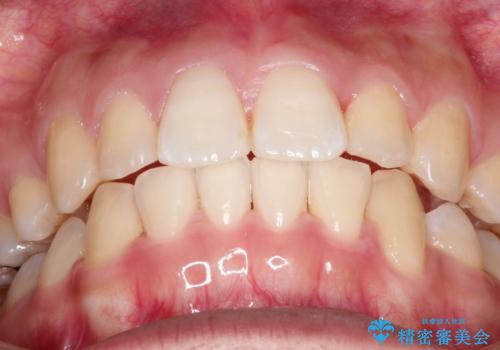

前歯が八重歯でガタガタ ワイヤーによる抜歯矯正

- 前歯のガタガタを主訴に来院されました。

前歯の重度のガタガタで、八重歯もある状態でした。

また右下の乳歯が残っており、永久歯が1本足りませんでした。

上顎両側と左下の前から4番目の歯と、右下の乳歯を抜歯して矯正することとなりました。